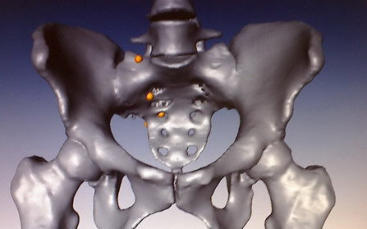

vermelden. Ich erinnert euch alle an die Bilder, die wir euch nach der Operation gezeigt haben. Hier ist es auf dem Foto noch einmal zu

sehen. Es ist ihr operativ das rechte Wadenbein aus dem Bein entfernt und als Stütze in das Becken eingesetzt worden, dort, wo vorher

die Beckenschaufel war. Das ist schon ein Meisterwerk ärztlicher Kunst gewesen. Und Gott hat Gelingen und Segen dazu gegeben. Die

Schmerzen, die Puschel in den letzten Tagen mehr hatte als sonst, rühren jetzt daher, dass der Knochen etwa an der Stelle, auf die der

Pfeil zeigt, richtiggehend durchgebrochen ist. Die Ärzte sprechen von einem Ermüdungsbruch. Der Knochen ist in der Substanz während

der Zeit der Chemo und der dadurch beabsichtigten Verhinderung der Neubildung von Zellen (Zielpunkt waren natürlich die

Krebszellen) zurückgegangen und ermüdet. Das große Problem ist, dass nun noch weniger Stabilität da ist und der Knochen erst wieder

zusammenwachsen muss. Darum werdet ihr, wenn ihr hier reinschaut, nun wieder mehr Bilder von “Puschel im Liegen” sehen. Das ist

Regenerierung ist weit grösser als der eventuelle Schaden. Dr. Tunn, der Arzt, der Puschel operiert hat, war nicht wirklich erstaunt oder

enttäuscht, dass der eingesetzte Knochen gebrochen ist. Für ihn kam es nicht wirklich überraschend. Der Knochen hat offensichtlich während der

lange Chemozeit einiges an Substanz verloren und war demzufolge auch brüchig geworden. Er ist nicht an einer “Nahtstelle” gebrochen, sondern

im Knochen selbst. Und das ist nun eher positiv. Denn Gott hat den Knochen die Fähigkeit mitgegeben, einen sogenannten Kallus auszubilden, also

eine Art Wulst, der hinüberwächst zum anderen gebrochenen Ende. Dadurch wird der Knochen sogar in einem größeren Bereich sogar stärker als

vorher. Und das sogar unter normalen Bewegungen. Da die nun natürlich nicht zu heftig sein dürfen, hat Puschel zwei Probleme damit: die

vermehrten Schmerzen und die verordnete Bettruhe für mindestens 6-8 Wochen. Allerdings darf sie “normale Verrichtungen” selbst machen.